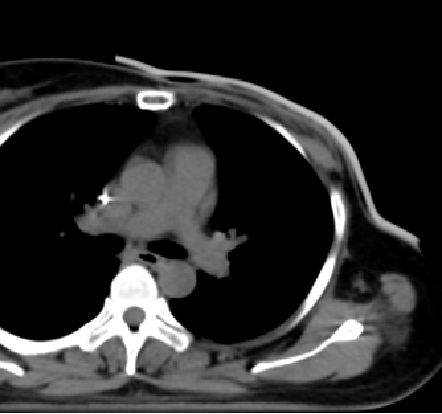

Conventional Bolus (white △ indicates air gaps)

3D Printed Bolus